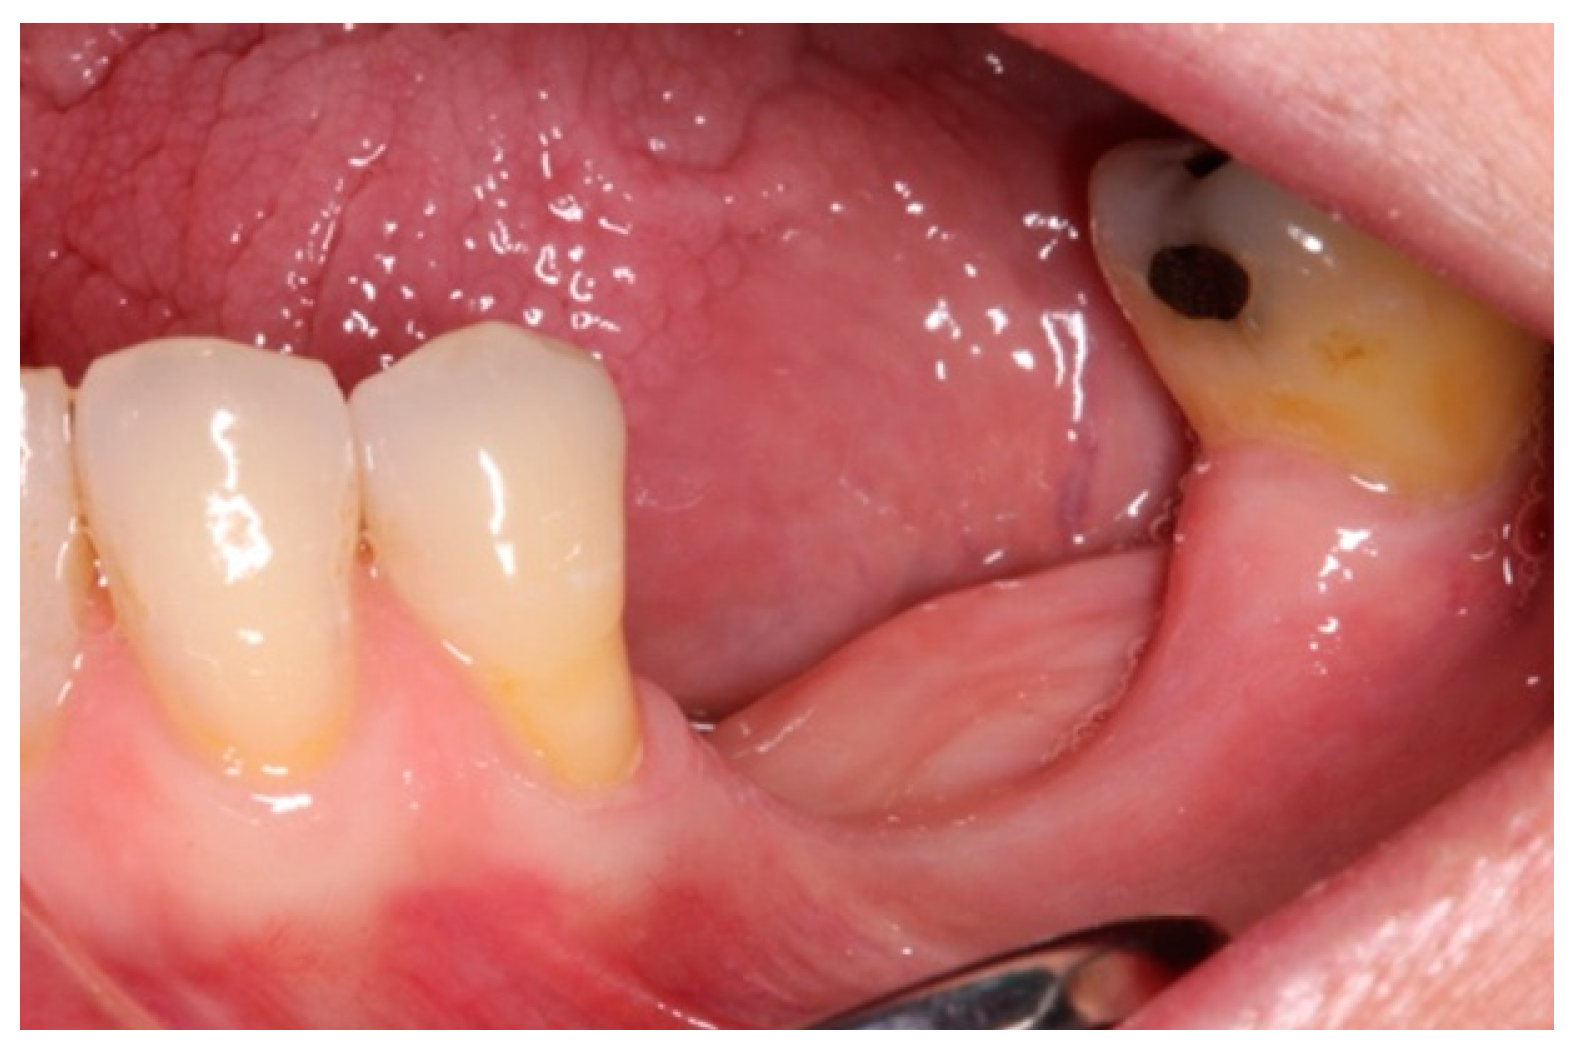

- On the day of surgery, the titanium mesh and the microscrews were removed (Figure 9). When the mesh was removed, a soft consistency was observed in the most coronally newly formed bone and it was decided to postpone the placement of the implants and allow it to ossify for another month and a half. A panoramic radiograph was taken after surgery (Figure 10).

- After 7 and a half months, the Avinent® 3.8 × 8.5 implants were placed in position 3.5 and 4 × 8.5 in position 3.6 (Figure 11). The torque of the implants was greater than 45 N/cm. The ISQ of both implants was taken, being 82 buccal and palatal for the implant in position 3.5 and an ISQ of 57 buccal and palatal for the implant in position 3.6. The bone gain obtained was 1.84 and 1.92 mm in width and 4.2 and 3.78 mm in height for positions 3.5 and 3.6. Simultaneously with the placement of the implants, a bone biopsy was performed between the implants, using a 2 mm bone trephine (Sanhigia, Bujaraloz, Spain) (Figure 12). Three months after the placement of the implants, the implants were rehabilitated using metal-ceramic screw-retained crowns.